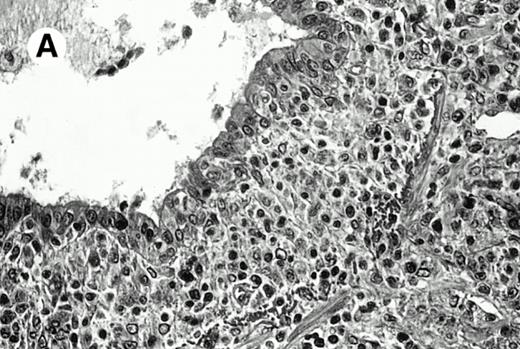

Three cases (cases no. 1 to 3) were located in the nasal cavity. The neoplastic infiltrate consisted of medium and/or large pleomorphic lymphoid cells (Fig 1)intermingled with variable numbers of small lymphoid cells, plasma cells, eosinophils, and histiocytes. Features of angiocentrism and angioinvasion, epitheliotropism, and areas of necrosis were observed in all three cases. Patient no. 4 presented with disease restricted to the lung and an open-lung biopsy was available. The neoplastic infiltrate was composed of large atypical lymphoid cells and was predominantly interstitial without extensive destruction of the normal architecture. Features of angiocentrism, angioinvasion, and epitheliotropism were present (Fig 2A and B). Case no. 5 involved the larynx, extending to the piriform sinus, the ventricle, and the arytenoid. One month later, the lymphoma disseminated to the subcutaneous tissue in the spinal region and biopsy specimens from both sites were available. The neoplastic cells were medium and large, with abundant clear cytoplasm and slightly irregular nuclei with dense chromatin. Epitheliotropism was present in the larynx mucosa. Small foci of necrosis and angiocentrism were seen without angioinvasion. Three patients presented with cutaneous disease. Cases no. 6 and 7 were comparable, as both histories started with necrotic subcutaneous nodules of the thigh, which on histologic analysis were characteristic of cytophagic histiocytic panniculitis without evidence of lymphoma (Fig 3A). Second excisional biopsies of cutaneous nodules obtained 7 and 5 months later, respectively, showed characteristic features of lymphoma in both cases (Fig 3B). However, in case no. 6, skin biopsy specimens showed an epidermotropic PML lymphoma extending to the dermis and the subcutaneous tissue, whereas in case no. 7, the neoplastic infiltrate consisted of a PSC confined to the subcutaneous tissue, admixed with benign histiocytes that showed phagocytosis. Patient no. 8 presented with recurrent skin lesions with spontaneous remission over a period of 10 years. The initial skin biopsies demonstrated an intense epidermotropic neoplastic infiltrate that extended to the superficial and deep dermis composed of atypical PML cells. All cutaneous cases displayed features of angiocentrism, but angioinvasion was observed only in case no. 6 and foci of necrosis in cases no. 6 and 8.

Pulmonary pleomorphic large-cell γδ T-cell lymphoma (case no. 4). (A) Atypical lymphoid cells involve the bronchiolar wall and epithelium; (B) features of angioinvasion; note the preservation of alveolar structures (lung biopsy specimen with hematoxylin-eosin stain); (C) neoplastic cells strongly express TCR γδ. (Immunohistochemical staining on frozen sections with anti-δTCR1 antibody, APAAP technique.)